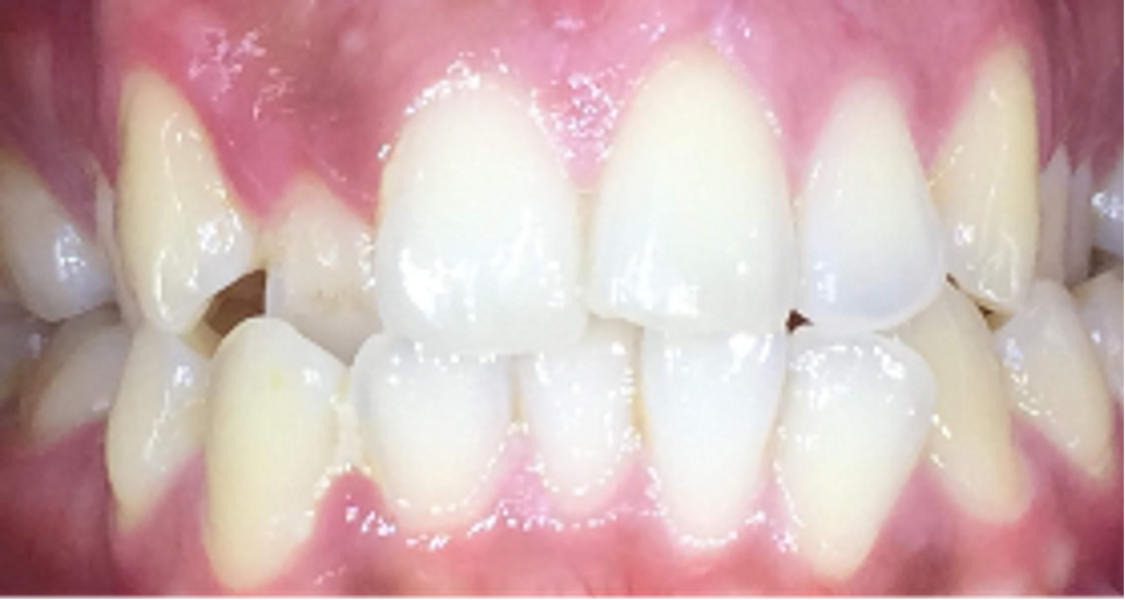

This 14-year-old patient too desired improvement of her smile aesthetics with minimal restorative involvement. She did not want fixed orthodontics. She presented with significant excess gingival display in the maxilla, producing a gummy smile from tooth #14 to tooth #24 of about 3 mm. The patient also had a maxillary midline coinciding with her facial midline and a thin upper lip. The patient had a dental Class I relationship bilaterally with an overjet of 4 mm and overbite of 80% (Figs. 13–15). This patient presented with healthy gingival tissue of a medium-thickness biotype with no signs of local or general gingivitis and/or periodontitis. There were also no signs of any restorations or risk of or active dental caries.

After 18 months of fortnightly (39 maxillary and mandibular aligners) and then weekly changeovers of two refinement aligners, the result was achieved by masking the gummy smile, broadening the smile and balancing the buccal corridors. The patient was placed into retention phase with clear thermoplastic retainers made by our laboratory using the PRO 4K.

The overjet was reduced to 1.5 mm and the overbite finished at 30%. There was no need for any restorative or soft-tissue augmentation. Anterior maxillary intrusion of 1.5–2.9 mm was achieved, reducing the gummy smile from tooth #13 to tooth #23 (Figs. 16 & 17).

Fig. 14: Close-up view of the patient’s smile.

Fig. 15: Orthodontic digital simulation using Invisalign software to show the pre-treatment position (blue) and the predicted result after treatment (white).